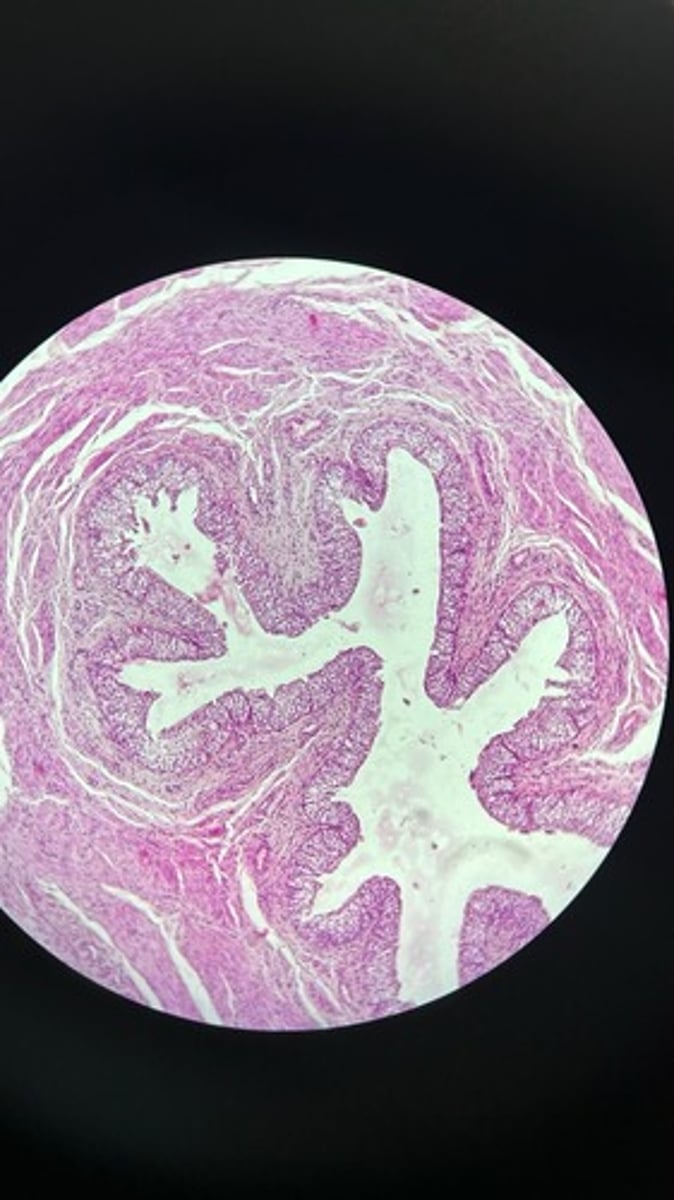

Uterus HE

Uterus HE

Uterus HE

Uterus HE